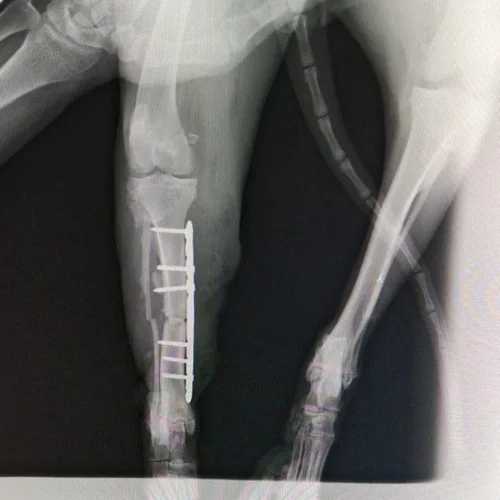

A Pantufa, com menos de um ano de vida, foi brutalmente atropelada em uma BR e chegou até nós com fraturas graves — três patas quebradas, sendo duas dianteiras e uma traseira. Uma das patinhas dianteiras estava com osso exposto, e por esse motivo precisou ser amputada imediatamente. Houve até quem sugerisse a eutanásia, mas nós não queríamos desistir dela. A Pantufa queria viver, e nós escolhemos lutar ao lado dela.

Com a ajuda de muitas pessoas de coração incrível, conseguimos custear os primeiros atendimentos, exames, raio-x e a cirurgia para colocação da placa. Porém, os custos continuam: